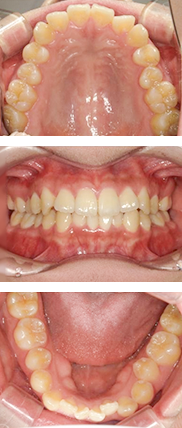

インビザライン症例(前歯のみ動かすマウスピース矯正)

治療費用:33,000円+66万円+5,500円×10+55,000円(リテーナー)

マウスピースの中にホワイトニング剤(6,600円)を入れることで、同時にホームホワイトニングを行いました。

矯正前

矯正中(約6ヶ月後)

矯正後(約4ヶ月後)